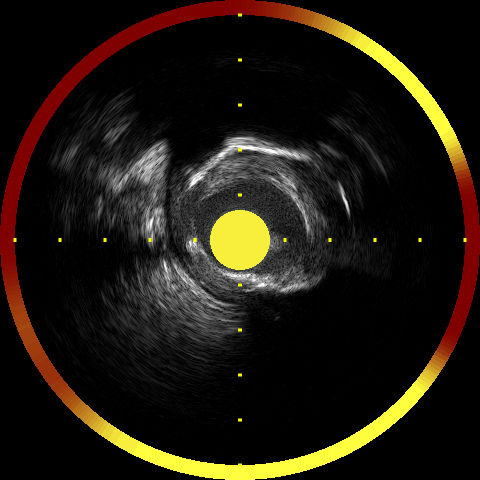

冠動脈では光の進行方向に脂質コアプラークがあるかどうかを、このような図を用いて評価します。黄色がLipidのあるところで、赤はないところです。

冠動脈の長軸方向によって、下の図のように脂質コアプラークの分布が表され、これをケモグラムと呼びます。

脂質コアプラークの可能性を“[黄]=高い、[赤]=低い”の色彩を用いた“ケモグラム”で表示します。“ケモグラムブロック”は縦 1 ブロック 2 mm 毎に表示し、LCP の可能性を 4 段階「(低い)赤 - 橙 - 薄橙 - 黄(高い)」で表示します。それぞれの確率 P 値が 0.57 未満(信頼性: 85%未満)の時は赤、0.57-0.84の時は橙、0.84-0.98の時は薄橙、0.98 以上(信頼性: 95%以上)の時は黄で表示されます(TVCカテーテル添付文書より)。